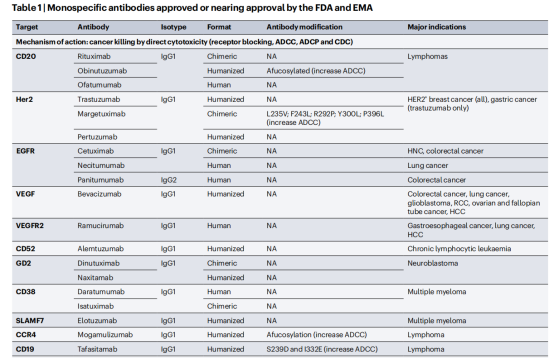

单特异性抗体是与靶抗原结合的全长免疫球蛋白,它有5种亚型IgG、IgM、IgA、IgE和IgD,其中只有IgG4与新生儿Fc受体(FcRn)结合,导致半衰期长约21天。大多数FDA和EMA批准的抗体以及正在开发的抗体使用IgG抗体格式,IgG抗体有四个亚类(IgG1、IgG2、IgG3和IgG4),大多数治疗性抗体利用IgG1亚类。单特异性抗体一般靶向抗原是细胞表面蛋白,主要是在实体癌中过表达的生长因子受体,对于血液系统恶性肿瘤,抗体通常针对由不同免疫细胞亚群表达的细胞表面糖蛋白(也称为分化簇(CD)标记物)。

单特异性抗体结合癌细胞上的抗原,通过多种机制导致细胞死亡,包括生长因子受体(如人表皮生长因子受体2(HER2))的生存信号中断,免疫细胞的激活(如自然杀伤(NK)细胞介导的抗体依赖性细胞毒性(ADCC)和巨噬细胞介导的抗体依赖性细胞吞噬(ADCP))。以及通过激活补体级联反应(补体依赖性细胞毒性(CDC))。免疫检查点阻断抗体结合并激活免疫细胞,如T细胞导联致免疫介导的癌细胞死亡。

单特异性抗体Fc工程:大多数IgG1抗体效应功能是由Fc结构域介导的,常见Fc结构域修饰包括聚焦化(从Fc区域去除焦点,以增加FcγrIIIa结合)或关键残基的氨基酸替换(如增加与Fc受体结合的S239D和I332E),这两种修饰均导致ADCC和ADCP增强。

免疫检查点抑制剂:针对免疫细胞调节检查点的单特异性抗体在癌症患者中显示出了显著的临床疗效。FDA和EMA批准的11种免疫检查点抑制抗体目前正在用于治疗20多种不同类型的癌症,包括肺癌、黑色素瘤、肾细胞癌、头颈部鳞状细胞癌,预计还有几种这些抑制性抗体将在不久的将来获得批准。